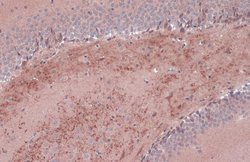

Keep as concentrated solution. Predicted reactivity: Mouse (100%), Rat (100%), Dog (100%), Cat (100%), Pig (100%), Chimpanzee (100%), Bovine (100%). Positive Control: mouse brain, rat brain, BDNF-transfected 293T. Store product as a concentrated solution. Centrifuge briefly prior to opening the vial.

| Immunohistochemistry (Frozen), Immunohistochemistry (Paraffin), Western Blot, Immunocytochemistry | |

| Human, Mouse, Rat | |